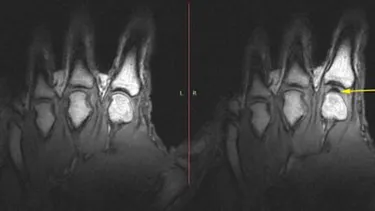

Röntgenbild Hände nach Fingerknacken